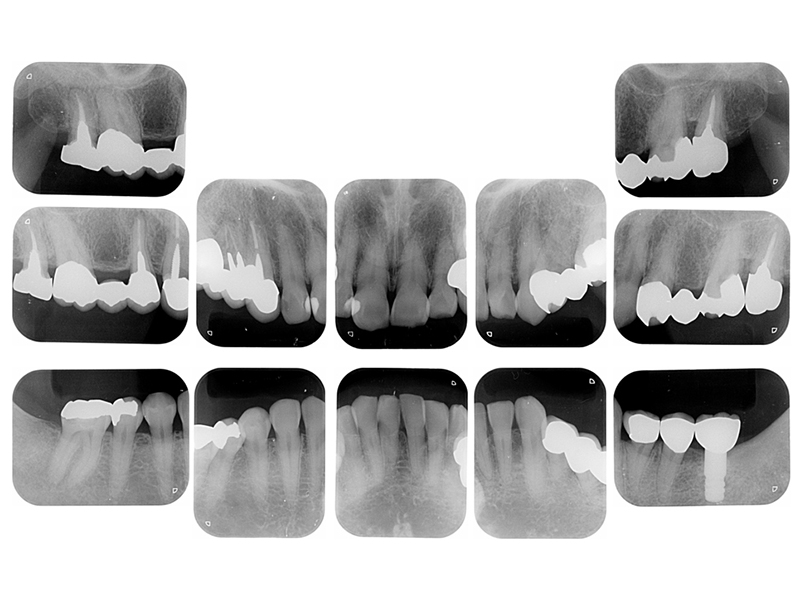

初診時X線写真